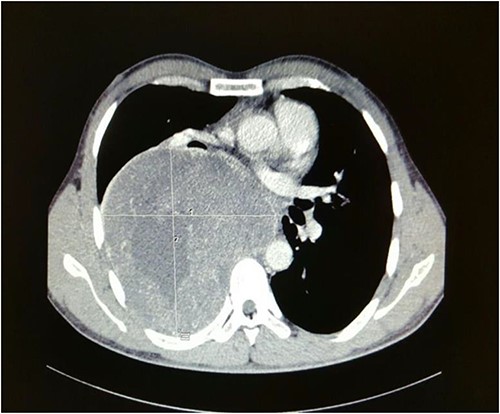

Computed tomography of the chest depicted a large well-defined heterogeneously enhancing right posterior mediastinal mass which measured 13.1 cm (width) × 12.6 cm (antero-posterior) × 17 cm (cranio-caudal), with foci of calcification, increased vascularity and areas of necrosis (Fig. 1).

Axial cut of a contrasted CT Thorax depicting a large right posterior mediastinal mass.

The right main pulmonary artery and right main bronchus were splayed and narrowed, with the esophagus displaced to the left. It extended superiorly to the mid-tracheal level. Although there was no evidence of right sided neuroforaminal widening, there was pressure erosion of right T4 and T5 posterior ribs. A bronchoscopy performed revealed external compression affecting the right and left main bronchus and part of the carina, with no evidence of bronchomalacia. A baseline lung function test done also showed severe obstructive pattern with an FEV1 of 1.11 L (29% predicted), an FVC of 2.29 L (50% predicted) as well as an FEV1/FVC ratio of 49. A CT-guided biopsy of the posterior mediastinal mass was subsequently performed, and histopathological assessment showed presence of spindled-shaped and ganglion-like cells with no evidence of malignancy, suggestive of ganglioneuroma.